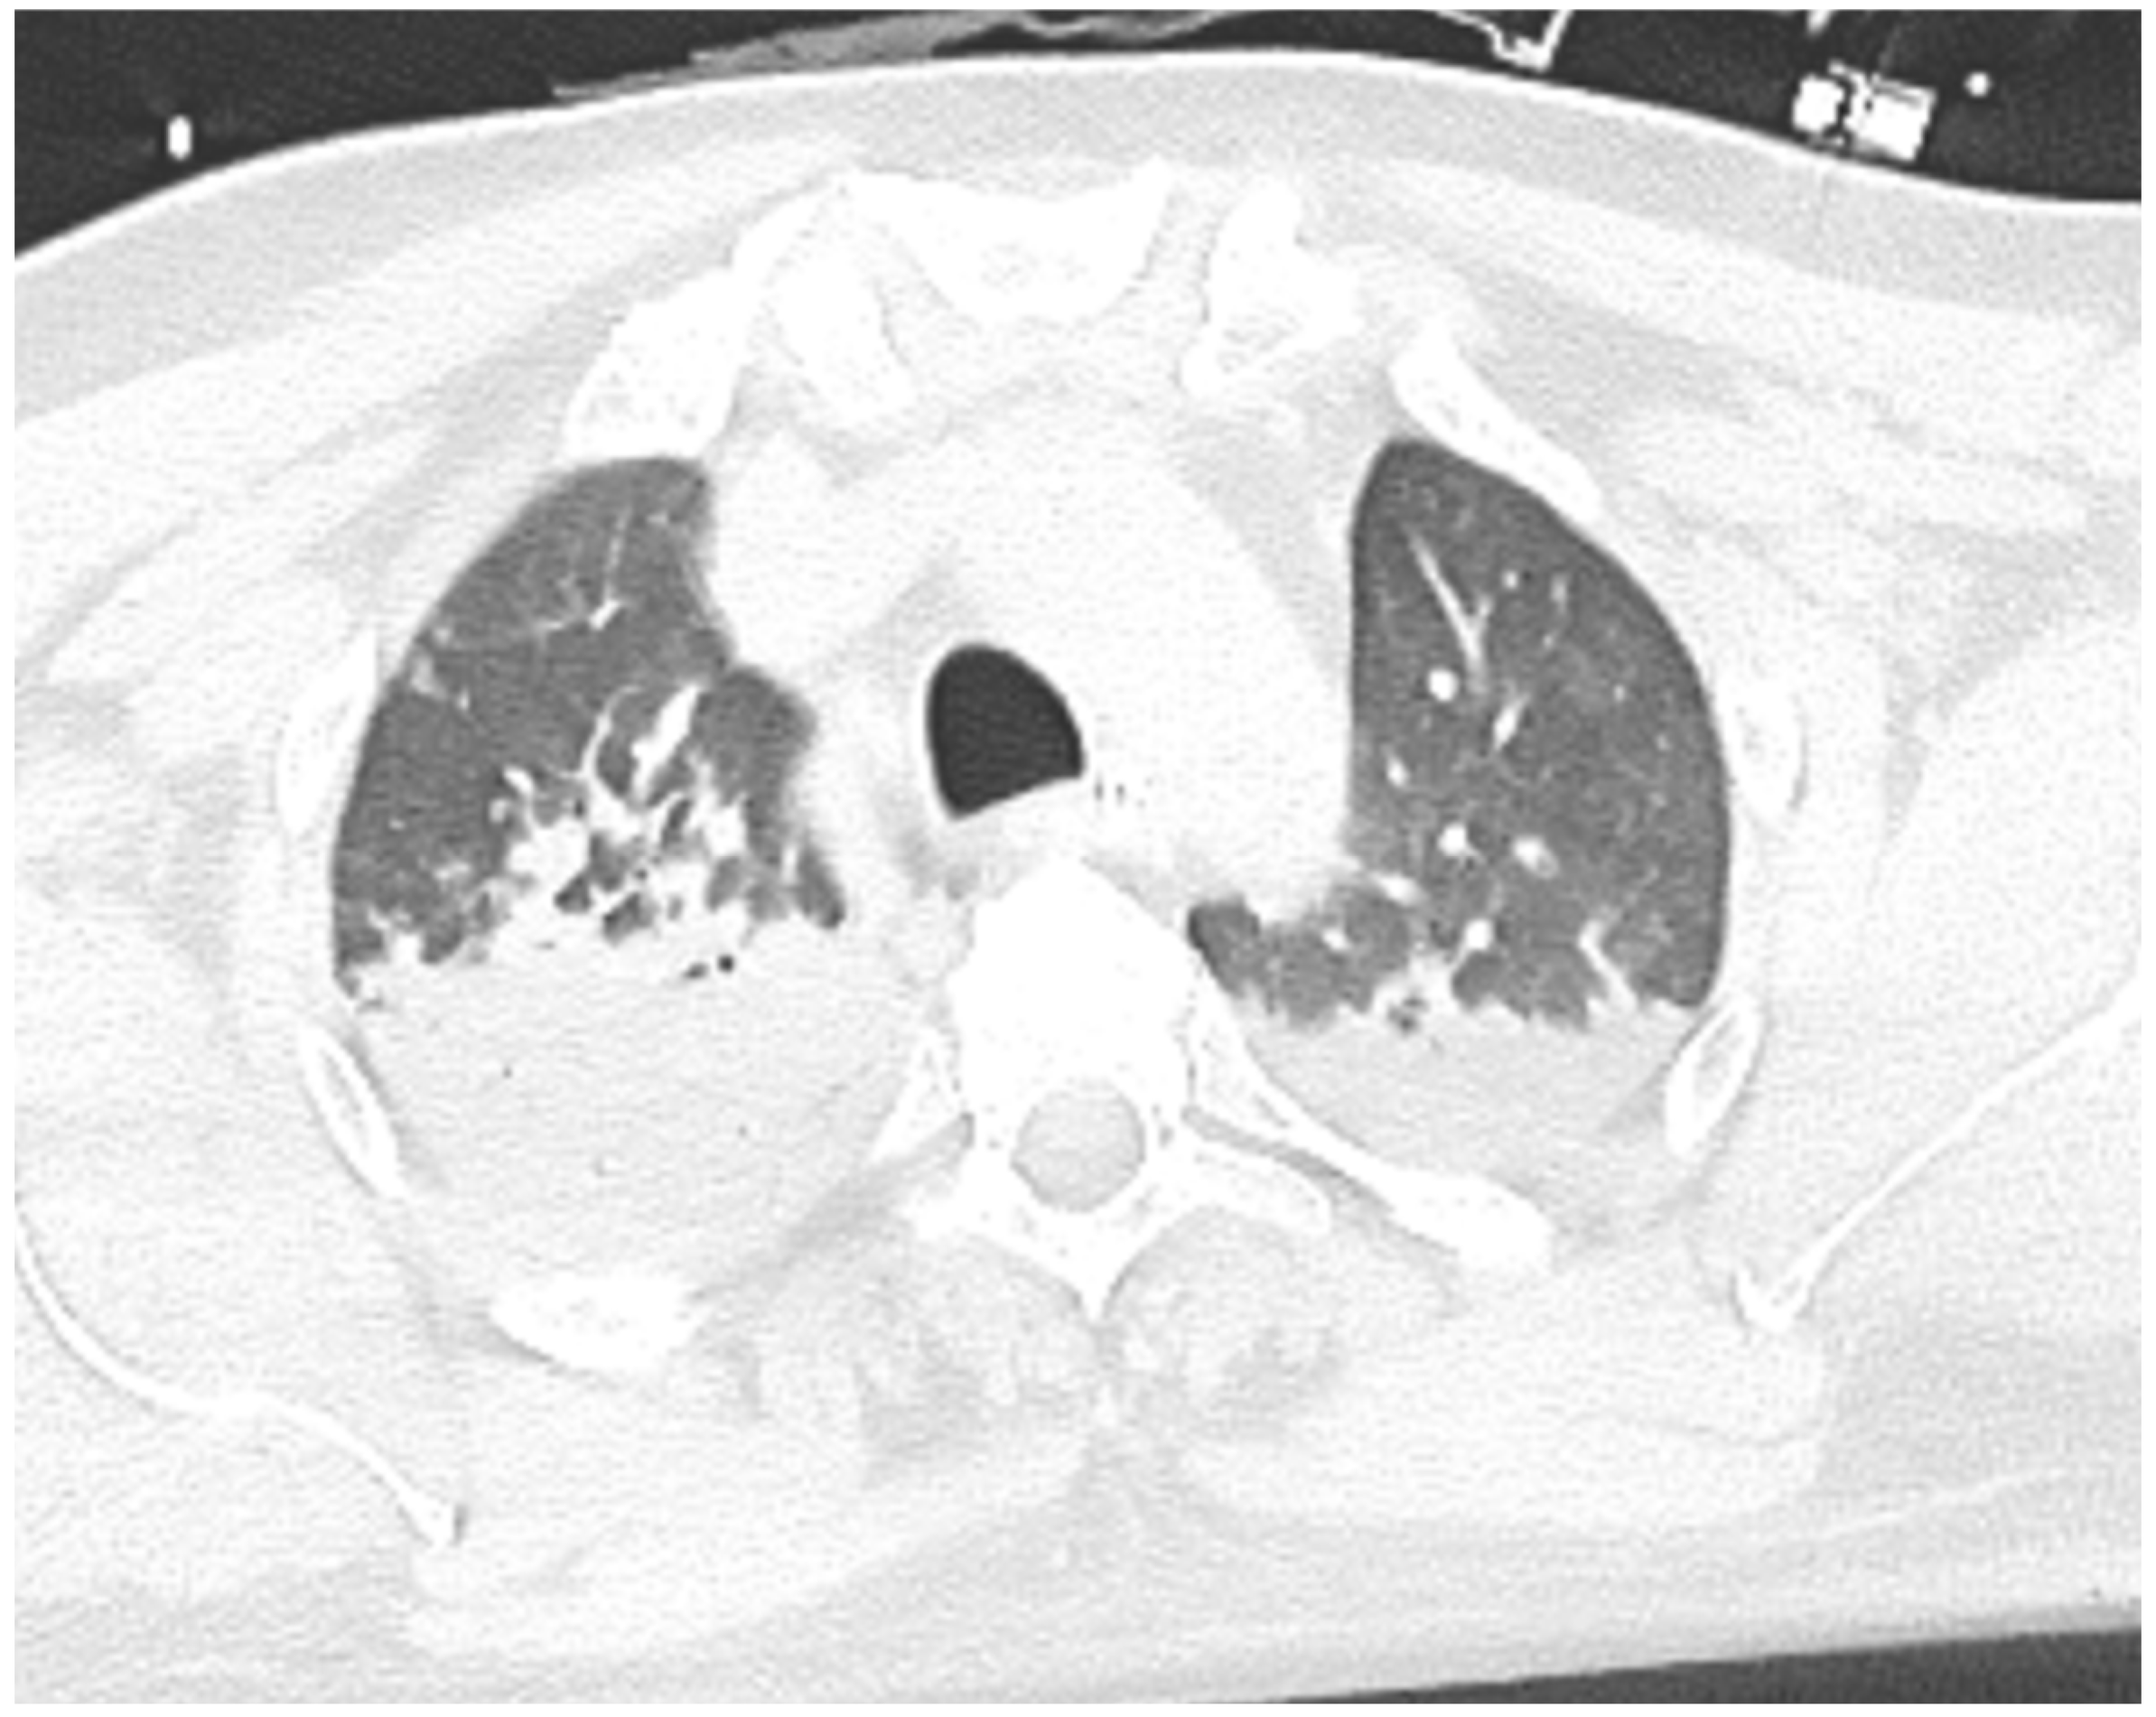

| Index case | 47 | M | DM | Aromatic hydrocarbons | Dyspnea | Diffuse ST elevation, NSVTs, and one episode of VF | 1.6 ng/mL | Severe biventricular dysfunction and right ventricular dilatation (LV EF 26%, RV FAC 16%, RV EDA 16 cm2/m2) | Neg | Edema and subepicardial LGE on lateral and inferior wall of LV; T1 mapping and extracellular volume increased | Acute lymphocytic myocarditis; molecular analysis revealed positive B19V transcriptional activity with significant viral load (>500 copies/μg) | Antiarrhythmic therapy with amiodarone and lidocaine; PSGB, vasoactive therapy with norepinephrine; inotropic support with levosimendan and dobutamine; heart failure treatment: ARNI, betablocker, MRA, and iSGLT2 | At 3-month follow-up: class I NHYA; echo with normalization of LVEF; no malignant arrhythmias at 24 h Holter ECG | no |